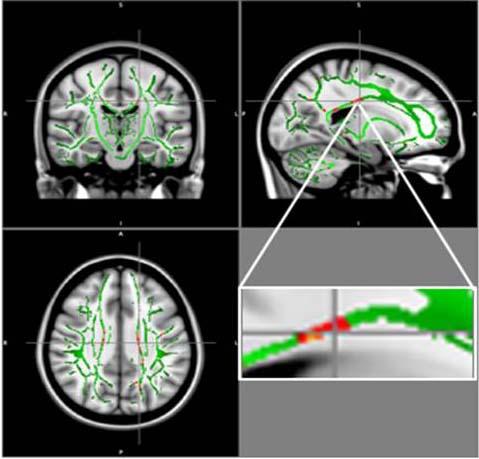

image: Reduction in fractional anisotropy (FA) in obese patients compared to the control group: At the intersection of the alignment vectors, a large cluster of FA decrease located in the corpus callosum on the left. In red: Reduction of FA in obese patients compared to controls, and FA skeleton (green), superimposed on the mean of FA images in sample.

For the new study, researchers compared DTI results in 59 obese adolescents and 61 healthy adolescents, ages 12 to 16 years. From DTI, the researchers derived a measure called fractional anisotropy (FA), which correlates with the condition of the brain's white matter. A reduction in FA is indicative of increasing damage in the white matter.

The results showed a reduction of FA values in the obese adolescents in regions located in the corpus callosum, a bundle of nerve fibers that connects the left and right hemispheres of the brain. Decrease of FA was also found in the middle orbitofrontal gyrus, a brain region related to emotional control and the reward circuit. None of the brain regions in obese patients had increased FA.